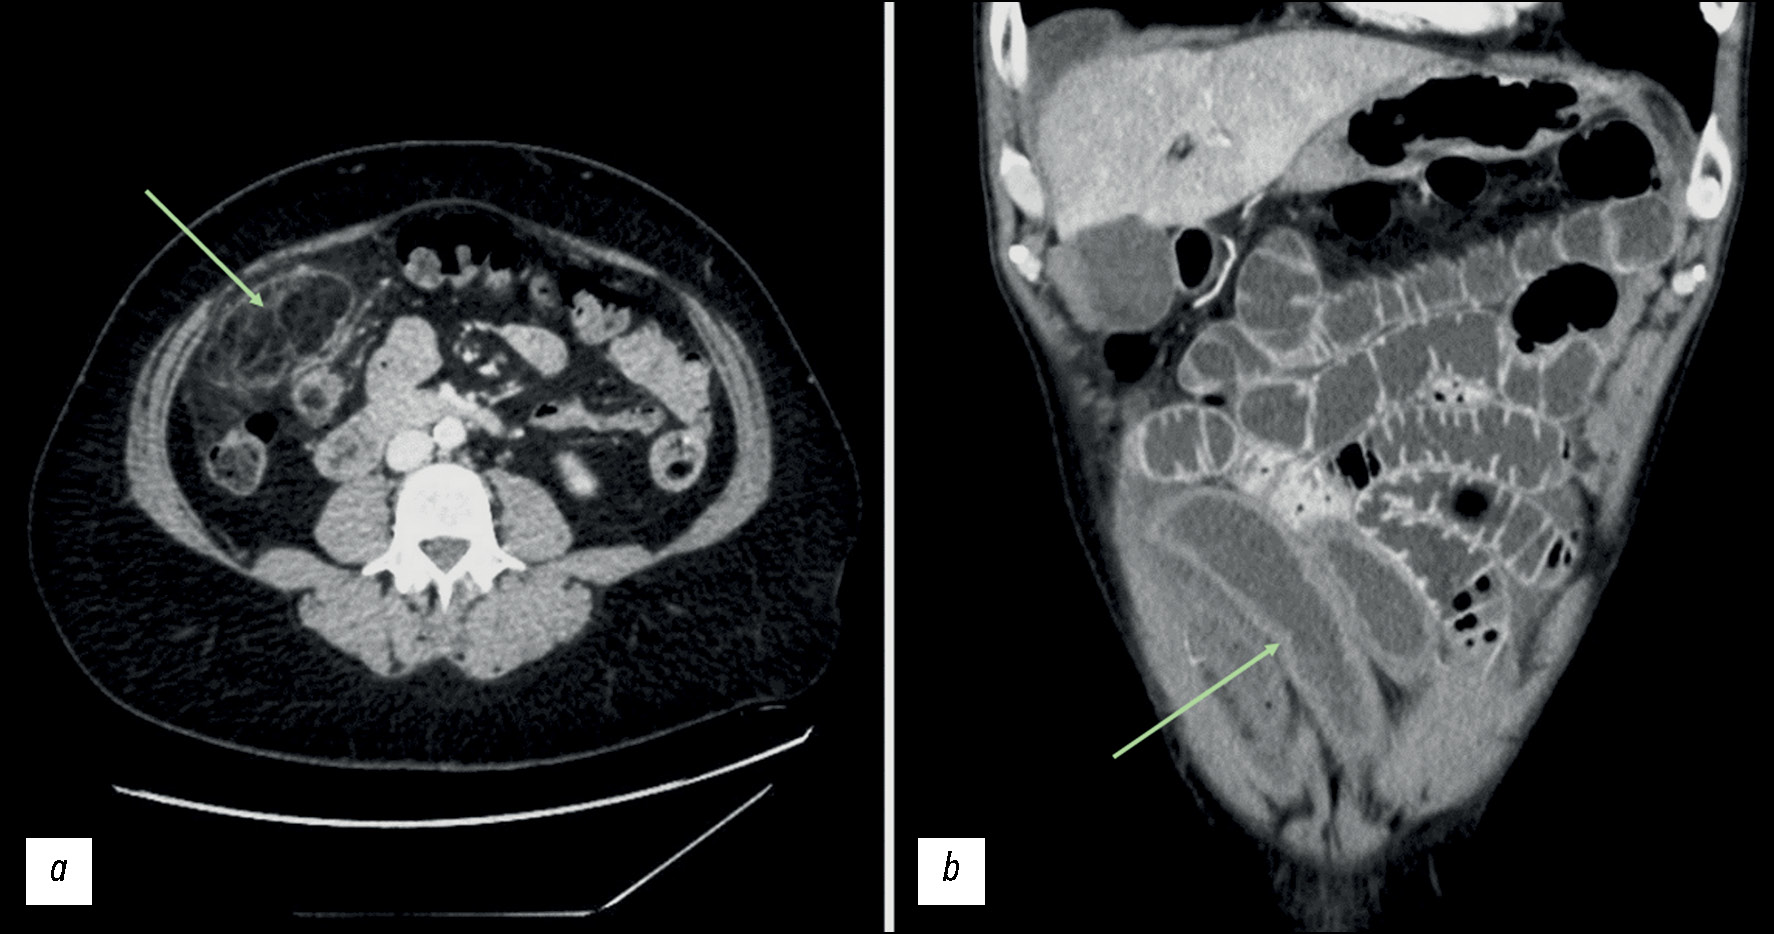

Несколько наглядных случаев изменений сосудов лёгких и кишечника у пациентов с COVID-19 показаны на рис. 1–3.

Рис. 2. Результаты компьютерной томографии, выполненной у пациента мужского пола, 33 лет, с COVID-19: a — тромб в заднем сегменте нижней доли левого лёгкого; b — плотное поражение мягких тканей в левом лёгком, прорастающее в область прилежащего ребра, и очаг деструкции в грудном позвонке.

Рис. 3. Результаты компьютерной томографии брюшной полости с контрастированием, выполненной у пациента мужского пола, 34 лет, с COVID-19: a — уплотнение жировой ткани сальника в правой нижней части живота, что свидетельствует о наличии инфаркта сальника; b — утолщение стенки подвздошной кишки в области дистального отдела с гипоконтрастированием по сравнению с прилегающей кишкой.